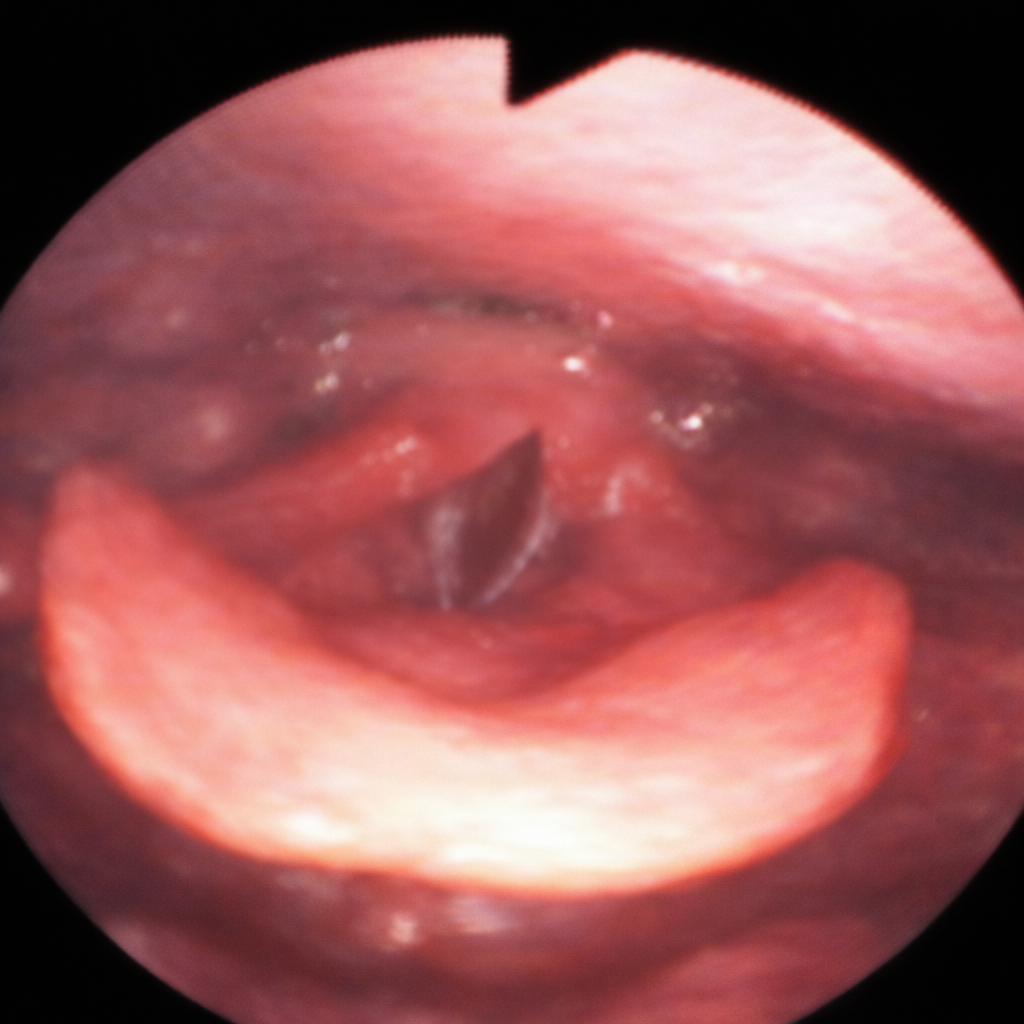

午前-60

75歳の女性。胃食道逆流症の既往があり、現在は在宅だが誤嚥性肺炎で入退院を繰り返している。口腔内の衛生状態は良好であり、普段の食事でむせはないという。嚥下内視鏡検査時の食物および飲料嚥下後の喉頭周囲の写真を別に示す。 誤嚥性肺炎の原因として疑われるのはどれか。2つ選べ。

a.食物

b.唾液

c.飲料水

d.逆流した胃内容物

解答を見る

b.d